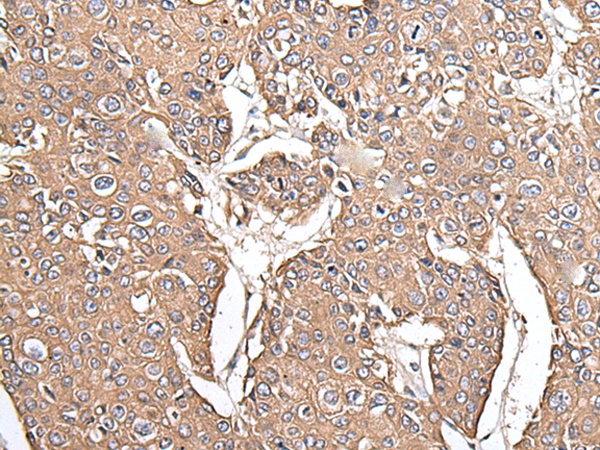

ELISA, IHC |

IHC positive control: |

Human prostate cancer and human lung cancer |

IHC Recommend dilution: |

40-200 |